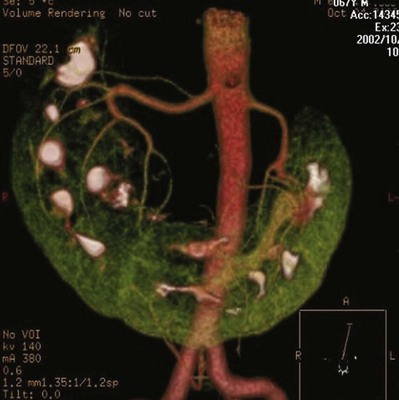

Three-dimensional (3D) volume-rendered CT is a valuable tool in the evaluation of patients undergoing renal surgery (Coll et al, 1999; Derweesh et al, 2003). CT can demonstrate vital information including the anatomy of the renal vasculature, orientation of the kidney, and characteristics of renal tumors, including location, depth of penetration into the kidney, relationship with collecting system, and segmental arterial supply to the tumor (Coll et al, 1999) (Figs. 54-12 to 54-14). CT is also able to characterize other surgically relevant processes, including renal arterial disease, nephrolithiasis, and hydroureteronephrosis (Herts, 2005).

Figure 54–12 Contrast-enhanced CT axial reconstruction demonstrating large right hypervascular mass suggestive of renal cell carcinoma.